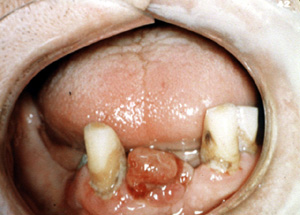

| El término

de épulis granulomatoso es aplicado a la situación dónde el tejido de

granulación no-específico prolifera fuera de un sitio. Esto

normalmente ocurre como resultado de una irritación que puede ser un

secuestro óseo u otro tejido necrótico que se encuentra en la lesión.

Esta masa de

tejido de granulación inflamado que crece fuera del avéolo post

exodoncia es la típica para el épulis granulomatoso. La biopsia es

obligatoria en semejante situación, porque hay lesiones malignas que se

manifiestan en igual forma.